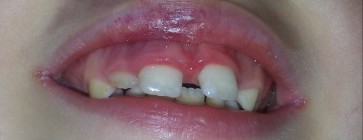

- OPIS PRZYPADKU. Fotobiomodulacja a osteogeneza - na podstawie autotransplantacji trzeciego zęba trzonowego